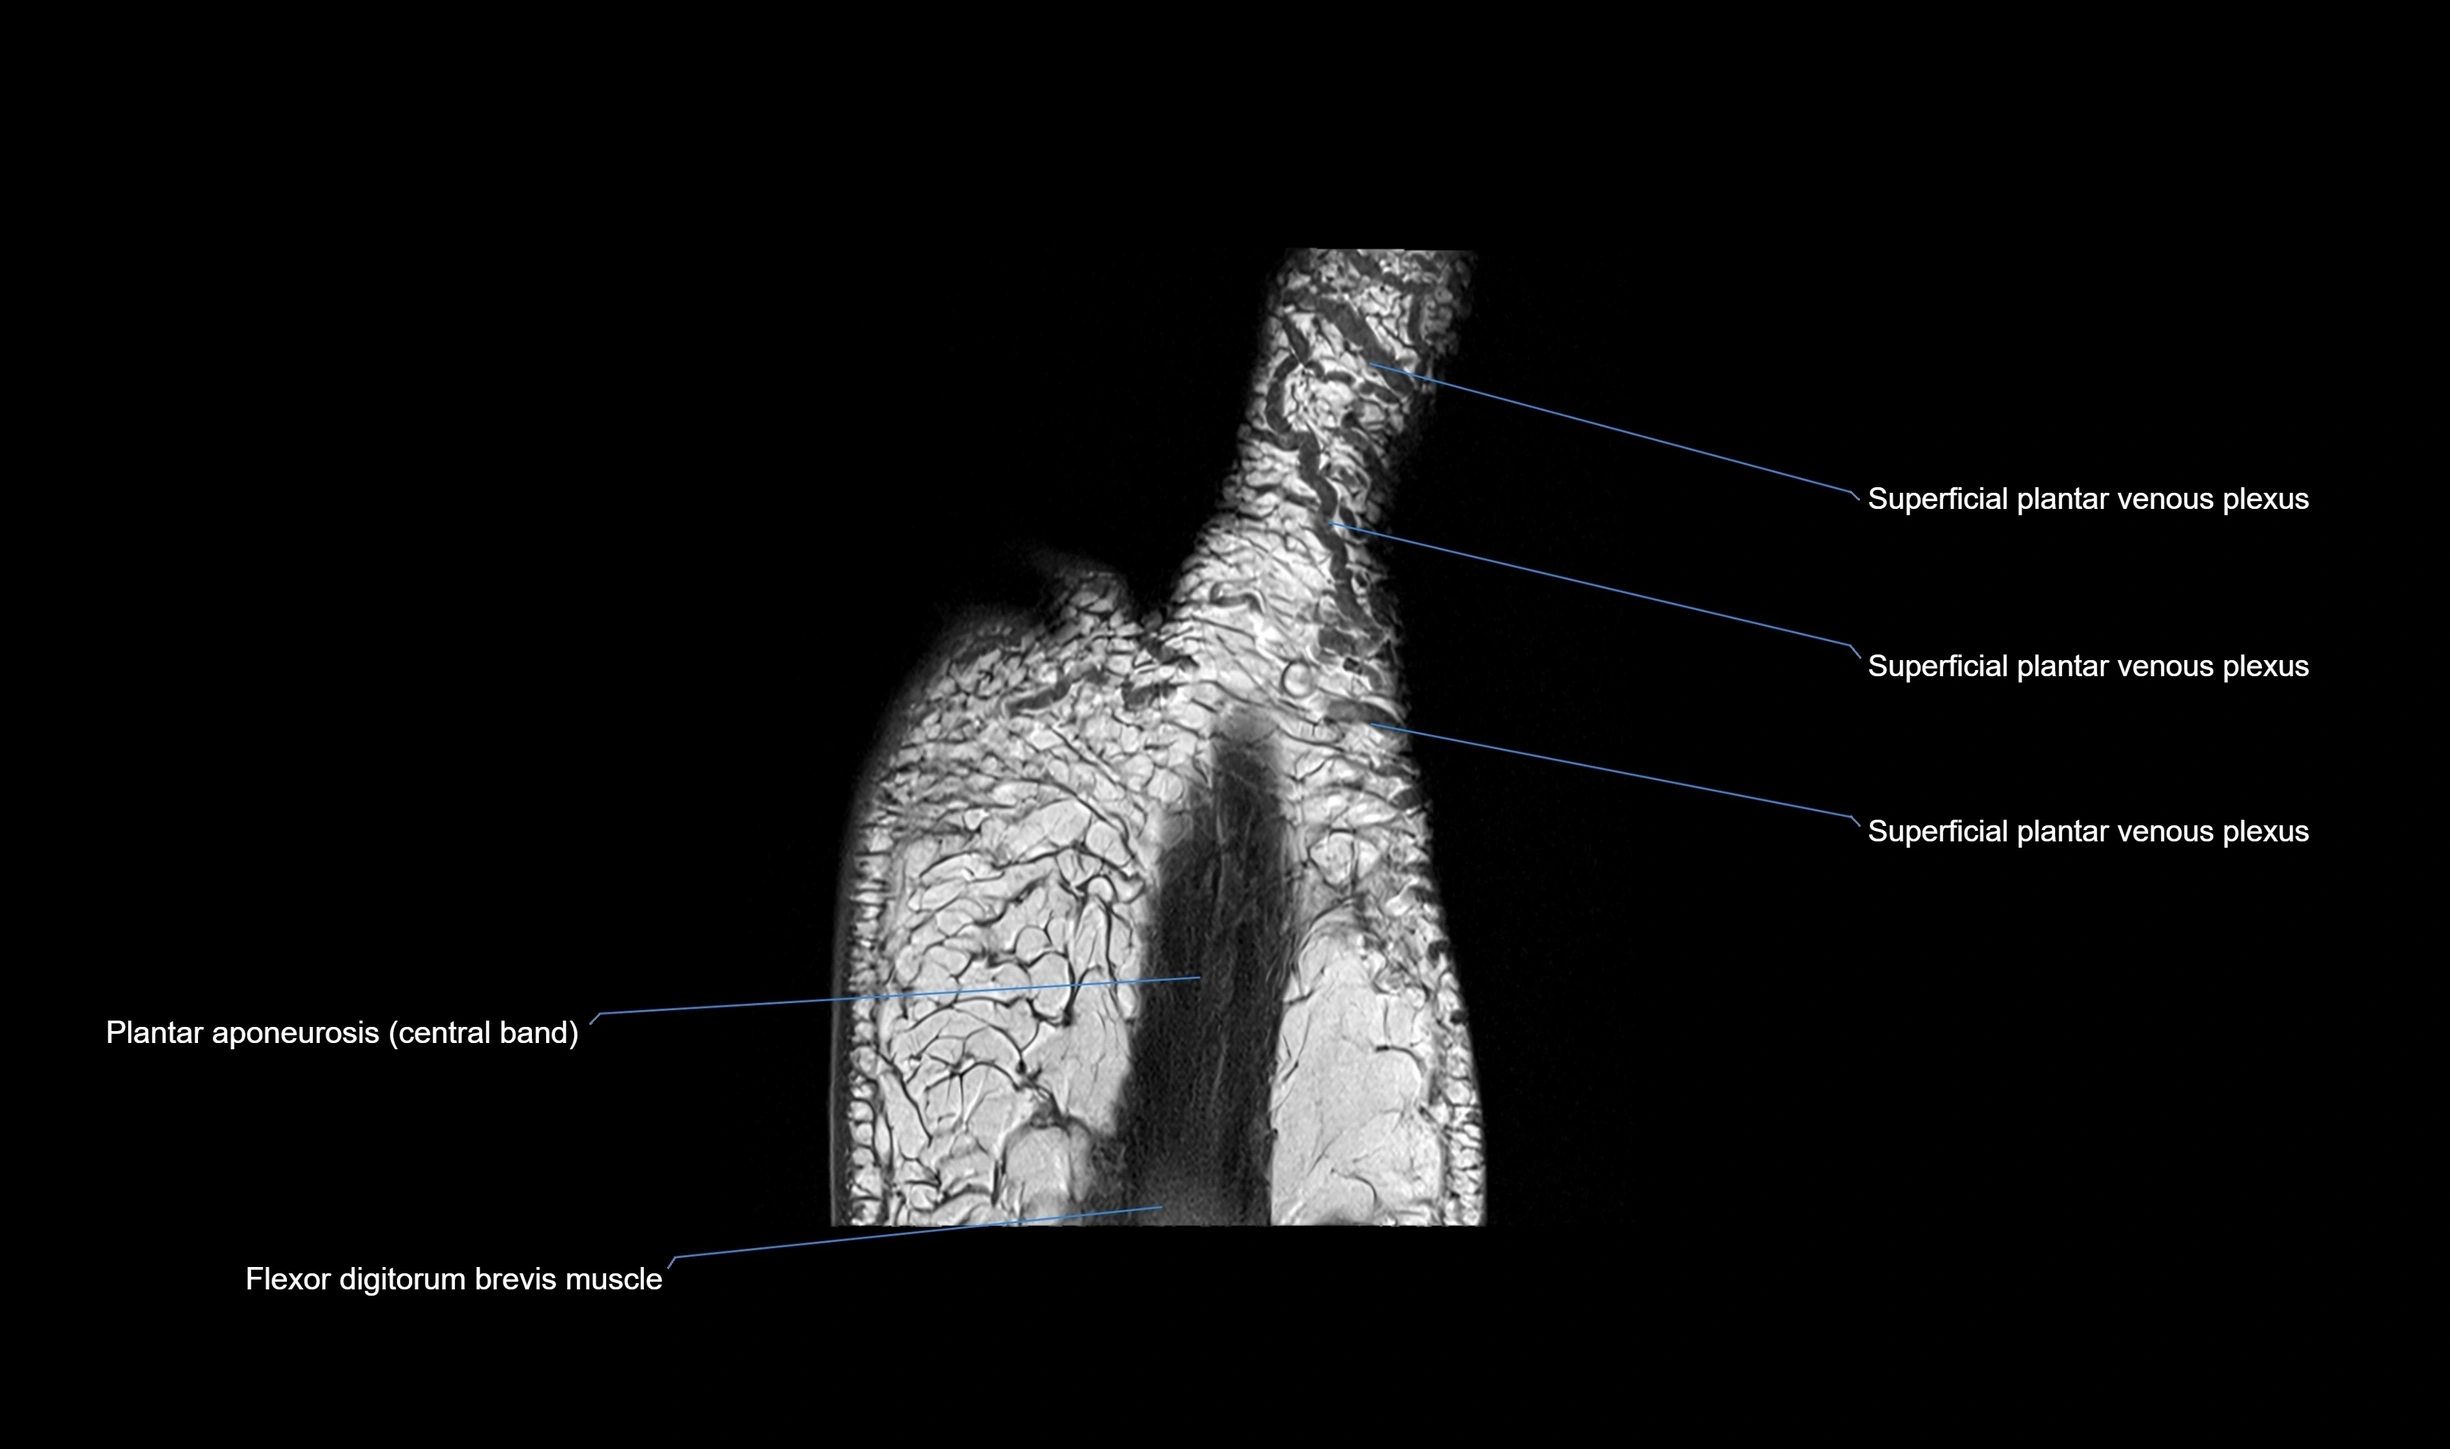

MRI image